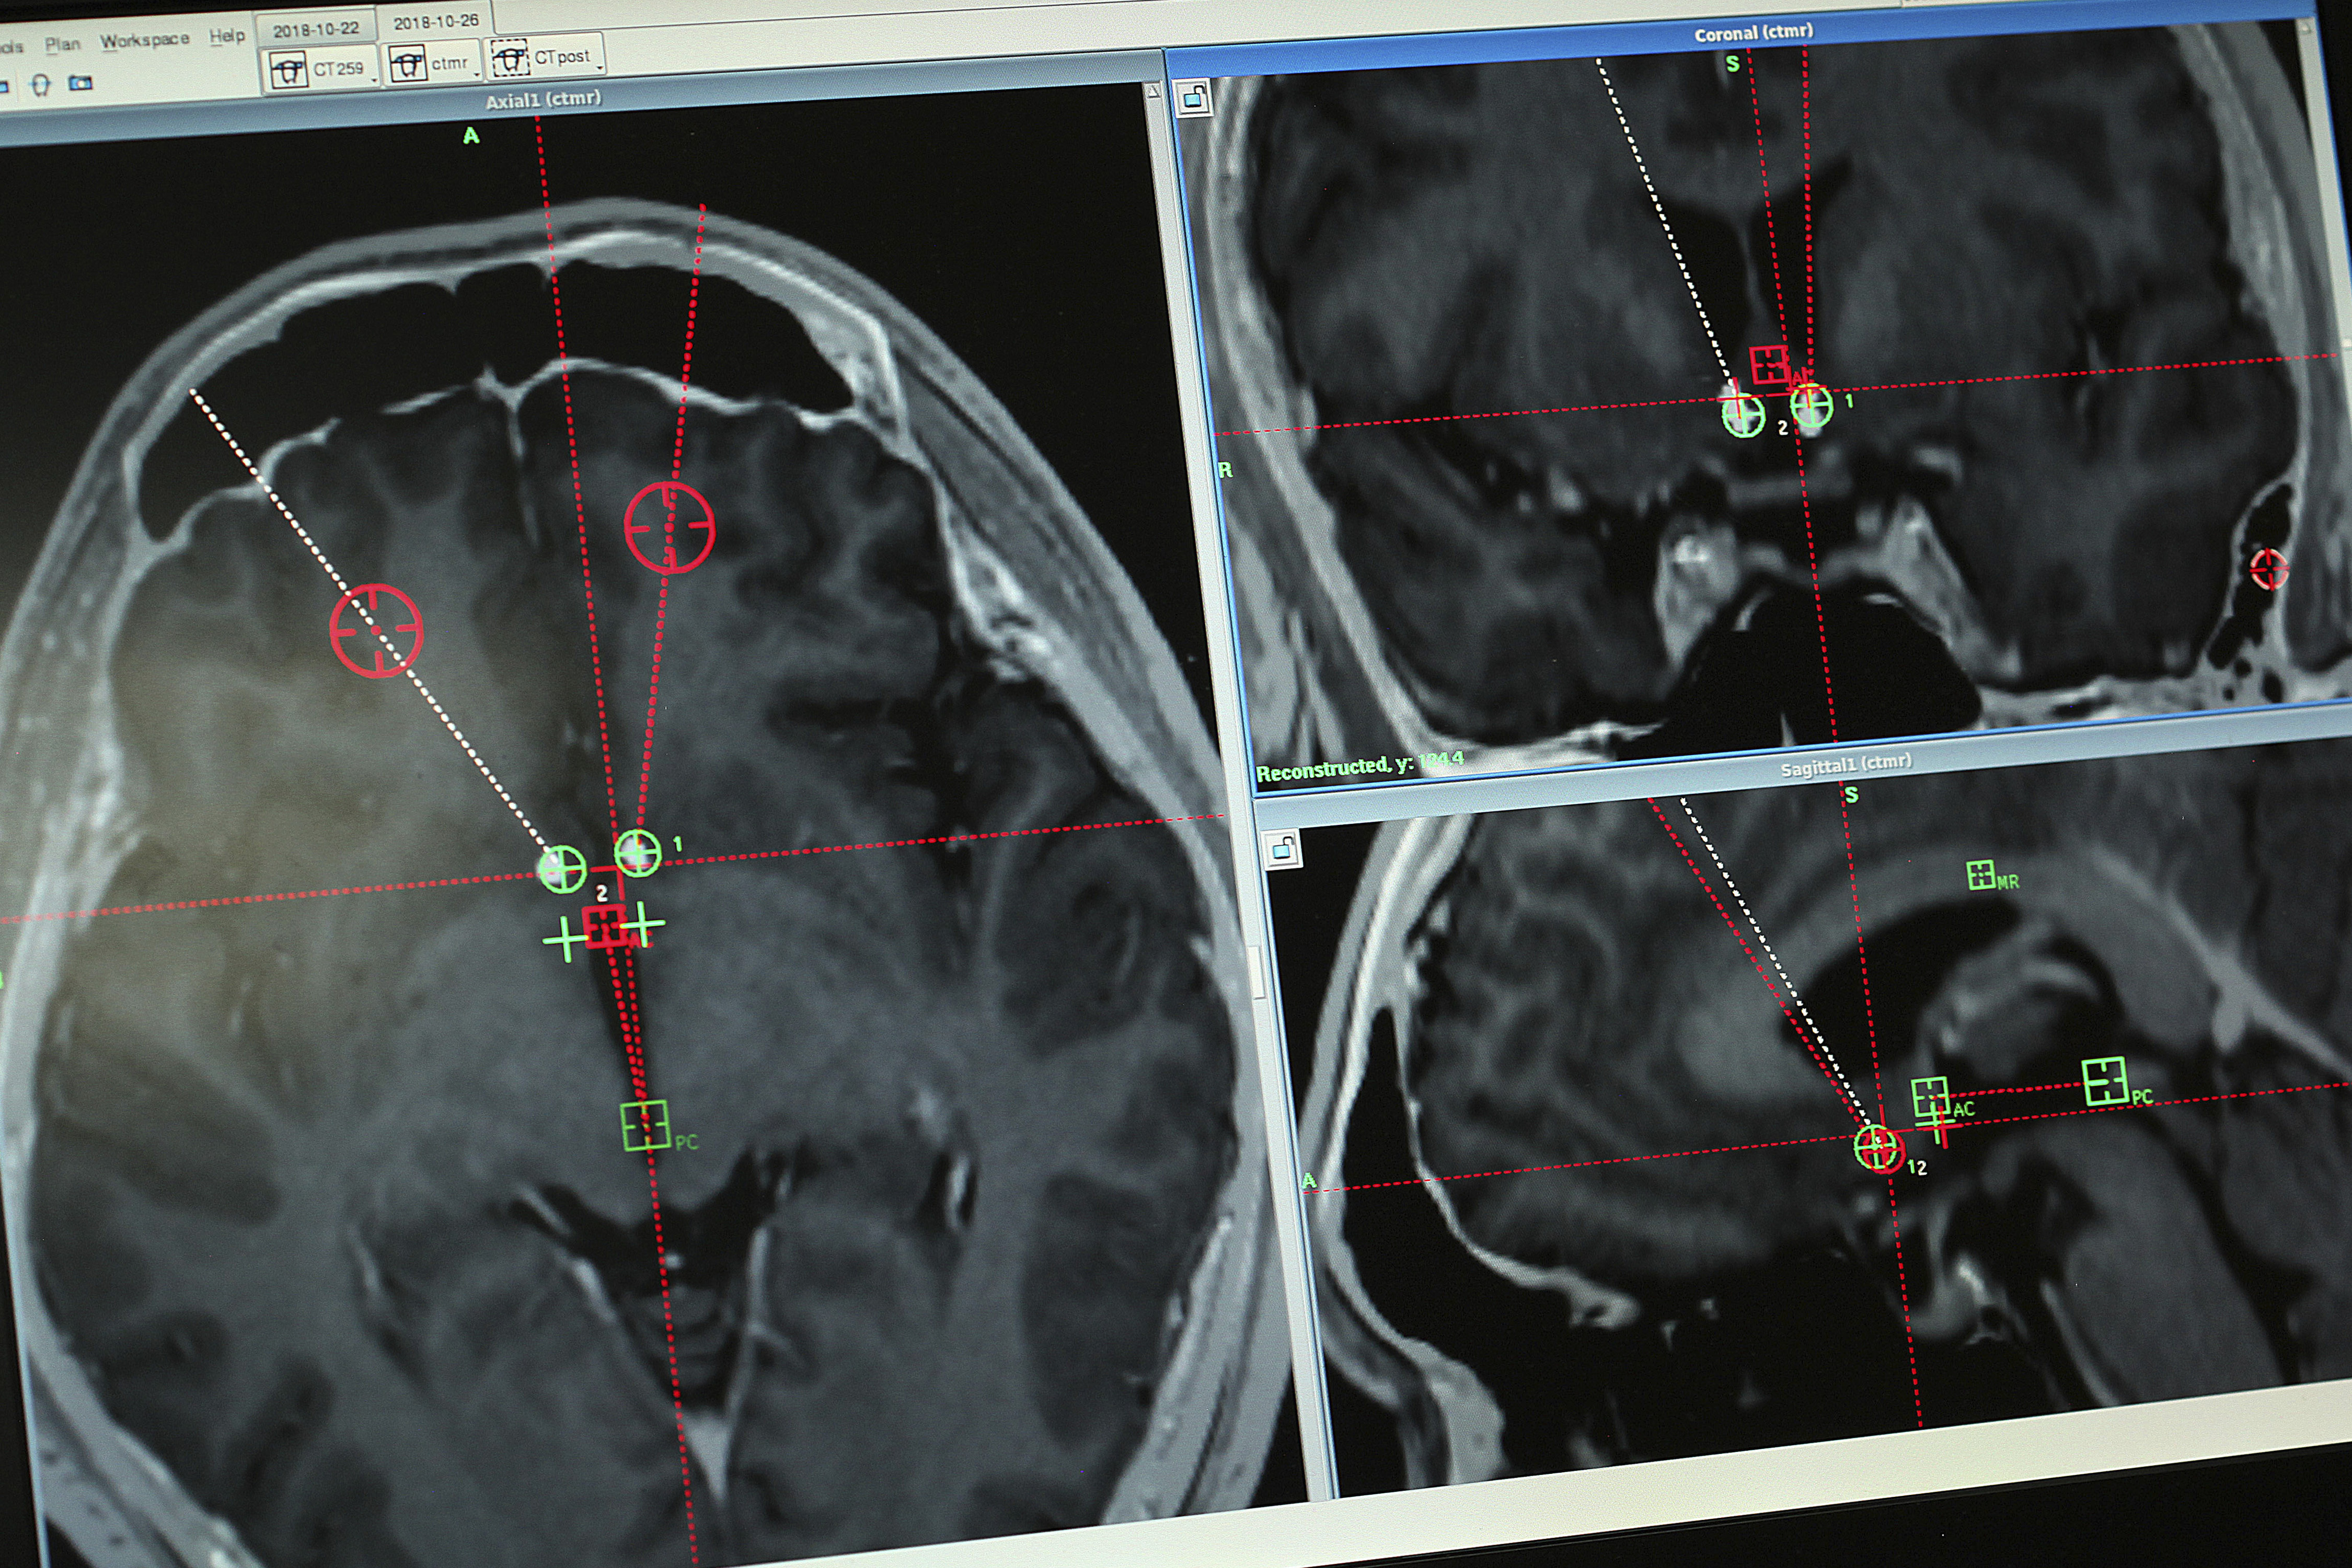

At 9 a.m. on a grey October Friday in Shanghai, Dr. Li drilled through Yan's skull and threaded two electrodes down to his nucleus accumbens, a small structure near the base of the forebrain that has been implicated in addiction.

The next day, he sat across from Dr. Li, who used a tablet computer to remotely adjust the machine thrumming inside Yan's head.